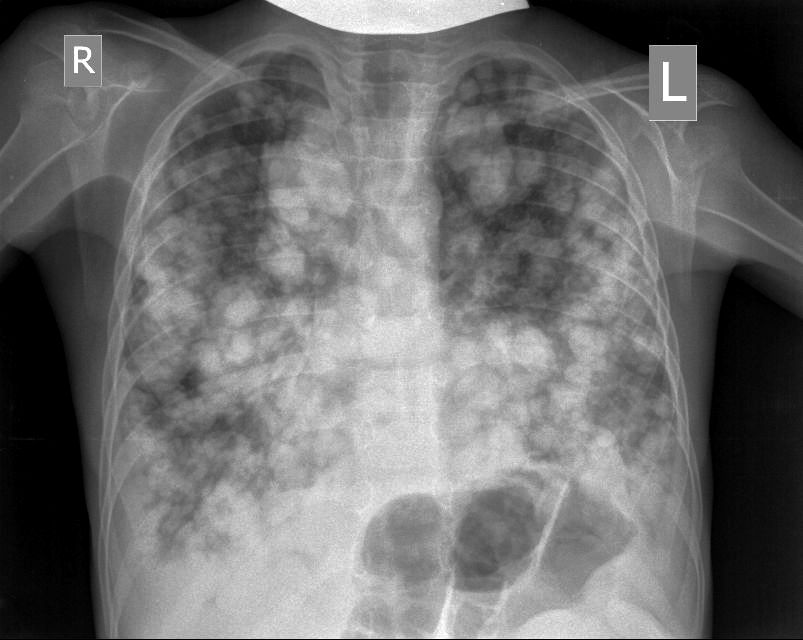

Предлагаю интересные изображения, полученные при сканировании лёгких через межрёберные промежутки и печень у ребёнка 4-х лет с подозрением на пневмонию

И в довершение - рентгенограмма лёгких для верификации ультразвуковых изображений.

CR0002.jpg

Я думал, что такое бывает только в старых книгах :shock: :o

ЦДК образований в лёгких не делал, если быть откровенным, порядок находок у этого пациента был следующим: МТС в печени - изменения в нижней доле правого лёгкого - забрюшиное пространство - левая почка - левое лёгкое - правое лёгкое - рентген лёгких. Картина в комплексе была и так ясна, т.е. то, что это MTS сомнений не вызывало. Ну а после патогномоничной рентгеновской картины - вопросов тем более не было.